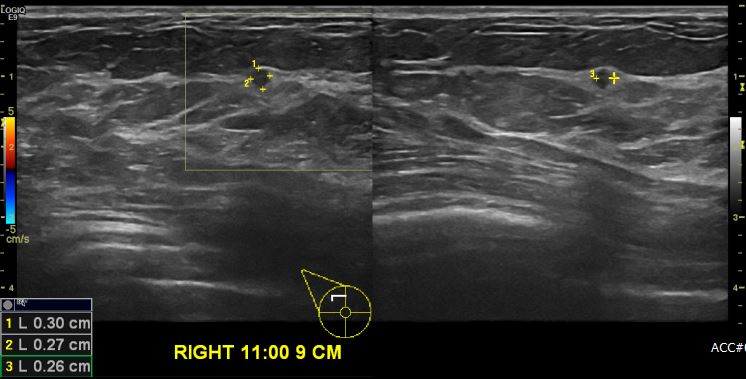

상기 환자 건강검진상 이상 소견으로 내원하신 50대 여성분으로 본원 초음파 시행 후

우측 유방 11:00시 방향에서 9cm 떨어진 거리의 의심스러운 혹 조직검사 시행하여

유측 침윤성 유관암 진단 되었습니다.